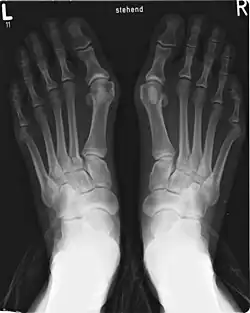

Paluch koślawy

Paluch koślawy (łac. hallux valgus), też haluks lub halluks – schorzenie wynikające m.in. z noszenia obuwia, zwłaszcza za ciasnego, na wysokim obcasie (szpilki) lub o wąskich noskach. Wysoki obcas niewłaściwie skonstruowanego obuwia powoduje przeciążenie przedniej części stopy, czego skutkiem jest obniżenie łuku poprzecznego i w następstwie poszerzenie przodostopia (płaskostopie poprzeczne). Natomiast spiczasty kształt butów bezpośrednio powoduje koślawe ustawienie palucha. Uważa się, że by wada mogła się rozwinąć, muszą istnieć predyspozycje w budowie stopy, natomiast obuwie powoduje nasilenie dolegliwości i przyspieszenie postępu deformacji[1].

Pod wpływem zniekształceń zmienia się biomechanika stopy. Nierównomiernie rozkłada się ciężar ciała, paluch nie jest już wystarczająco silnym punktem podparcia w czasie chodu. Pogarsza się wytrzymałość struktur stabilizujących stopę, osłabieniu ulegają mięśnie. W skrajnych przypadkach pojawia się stan zapalny torebki stawowej stawu śródstopno-paliczkowego palucha, obrzęk okolicy i bolesność okolicznych struktur połączona z obrzękiem w okolicy miejsca ulegającego deformacji. Może wystąpić również przerost nasady dalszej pierwszej kości śródstopia. Stan taki może być wskazaniem do leczenia operacyjnego, jednak poza deformacją, bardzo ważnym czynnikiem decyzyjnym jest empiryczne odczucie pacjenta, wskazujące na brak możliwości normalnego funkcjonowania w życiu codziennym[2]. Mniej zaawansowane zmiany poddają się na ogół leczeniu zachowawczemu polegającemu na noszeniu odpowiednich wkładek ortopedycznych oraz odprowadzaniu palucha na zewnątrz przez umieszczenie specjalnych wkładów silikonowych między paluch a drugi palec.